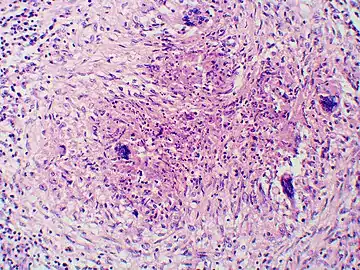

Once suspected, the diagnosis of blastomycosis can usually be confirmed by demonstration of the characteristic broad based budding organisms in sputum or tissues by KOH prep, cytology, or histology.[27] Tissue biopsy of skin or other organs may be required in order to diagnose extra-pulmonary disease. Blastomycosis is histologically associated with granulomatous nodules.